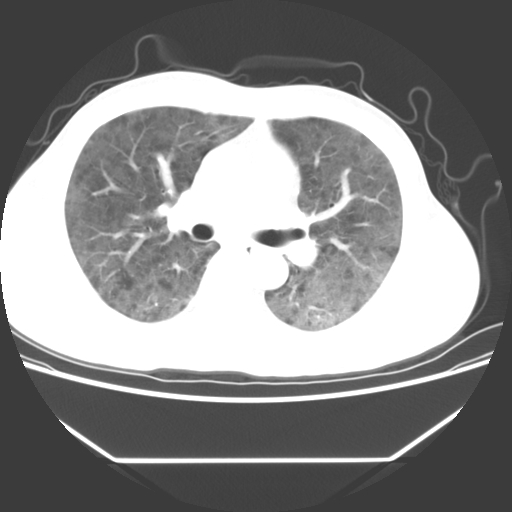

病人55岁,咳嗽,胸闷

忘了传病史了,病人55岁,咳嗽,胸闷

两肺部呈“毛玻璃”状改变,原因待查考虑感染性病变

病人是否发烧,两肺“磨玻璃”影,其间见空气支气管征和碎路石征。考虑肺泡蛋白沉着症。

两肺广泛对称磨玻璃样影,密度不均,考虑机遇性肺部感染。

双肺弥漫磨玻璃样病变,病史很重要。有感冒或发烧史,甲流不除外。无发烧可考虑肺泡蛋白沉积,但肺泡蛋白沉积边缘往往较清晰,与正常肺组织分界清晰

两肺弥漫间质性病变,考虑肺泡蛋白沉着症。建议进一步检查。

两肺“磨玻璃”影,其间见空气支气管征和碎路石征。考虑肺泡蛋白沉着症。